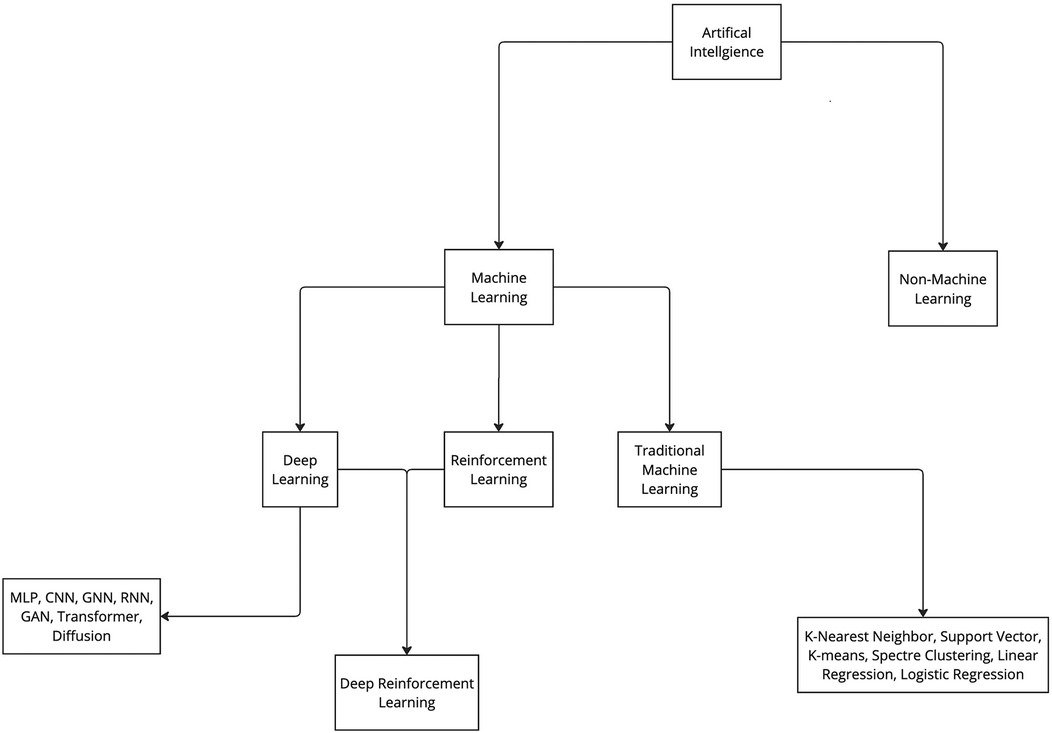

Various ML algorithms were used in these studies. For clarity, these algorithms can be categorized into deep learning and traditional ML (non–deep learning) algorithms (Figure 3). This review indicates that deep learning algorithms are significantly more popular than traditional ML algorithms. Specifically, 62 articles employed deep learning, whereas only 15 studies used traditional ML algorithms (Figure 2).

Figure 3. Categorization of artificial intelligence and machine learning. Artificial intelligence algorithms can be categorized into 2 groups: machine learning and non-machine learning. ML algorithms can be further categorized in 3 main groups: deep learning, reinforcement learning, and traditional machine learning. Furthermore, all these groups can be further divided into various subgroups. CNN, convolutional neural network; GAN, generative adversarial network; GNN, graph neural network; MLP, multilayer perceptron; RNN, recurrent neural network. Used with permission from Barrow Neurological Institute, Phoenix, Arizona.

With the advent of AI, the aim was to design a system that could operate intelligently and would be able to understand human language, perform mechanical tasks, solve complex computer-based problems, and return a human-like answer. Another skill humans possess is the ability to learn from our environment, as in language acquisition. When children are exposed to language and start to recognize patterns, they learn the rules of the language. They practice, evaluate their progress, receive feedback, and make adjustments. ML is a subset of AI that allows an AI system to accomplish a similar feat (Figure 3). The capacity of the system to learn is based on 3 factors: the data consumed, quantification of how incorrect the current behavior is compared to the ideal or model behavior, and a feedback mechanism to help guide and produce better future behavior (86). ML technology can predict stock market trends and serve as the foundation for self-driving cars, and its potential applications in medicine are equally, if not more, transformative. ML has been demonstrated to be effective in disease prediction (13), disease detection (14), radiologic interpretation (15), and enhancement of surgical precision (16), the last of which is the focus of this article.

These algorithms can be used in distinct learning paradigms, including supervised learning (93), unsupervised learning (86), and reinforcement learning (94). These 3 paradigms are the primary learning paradigms of ML, whereas deep learning is a distinct concept suitable for handling complex data structures (95).